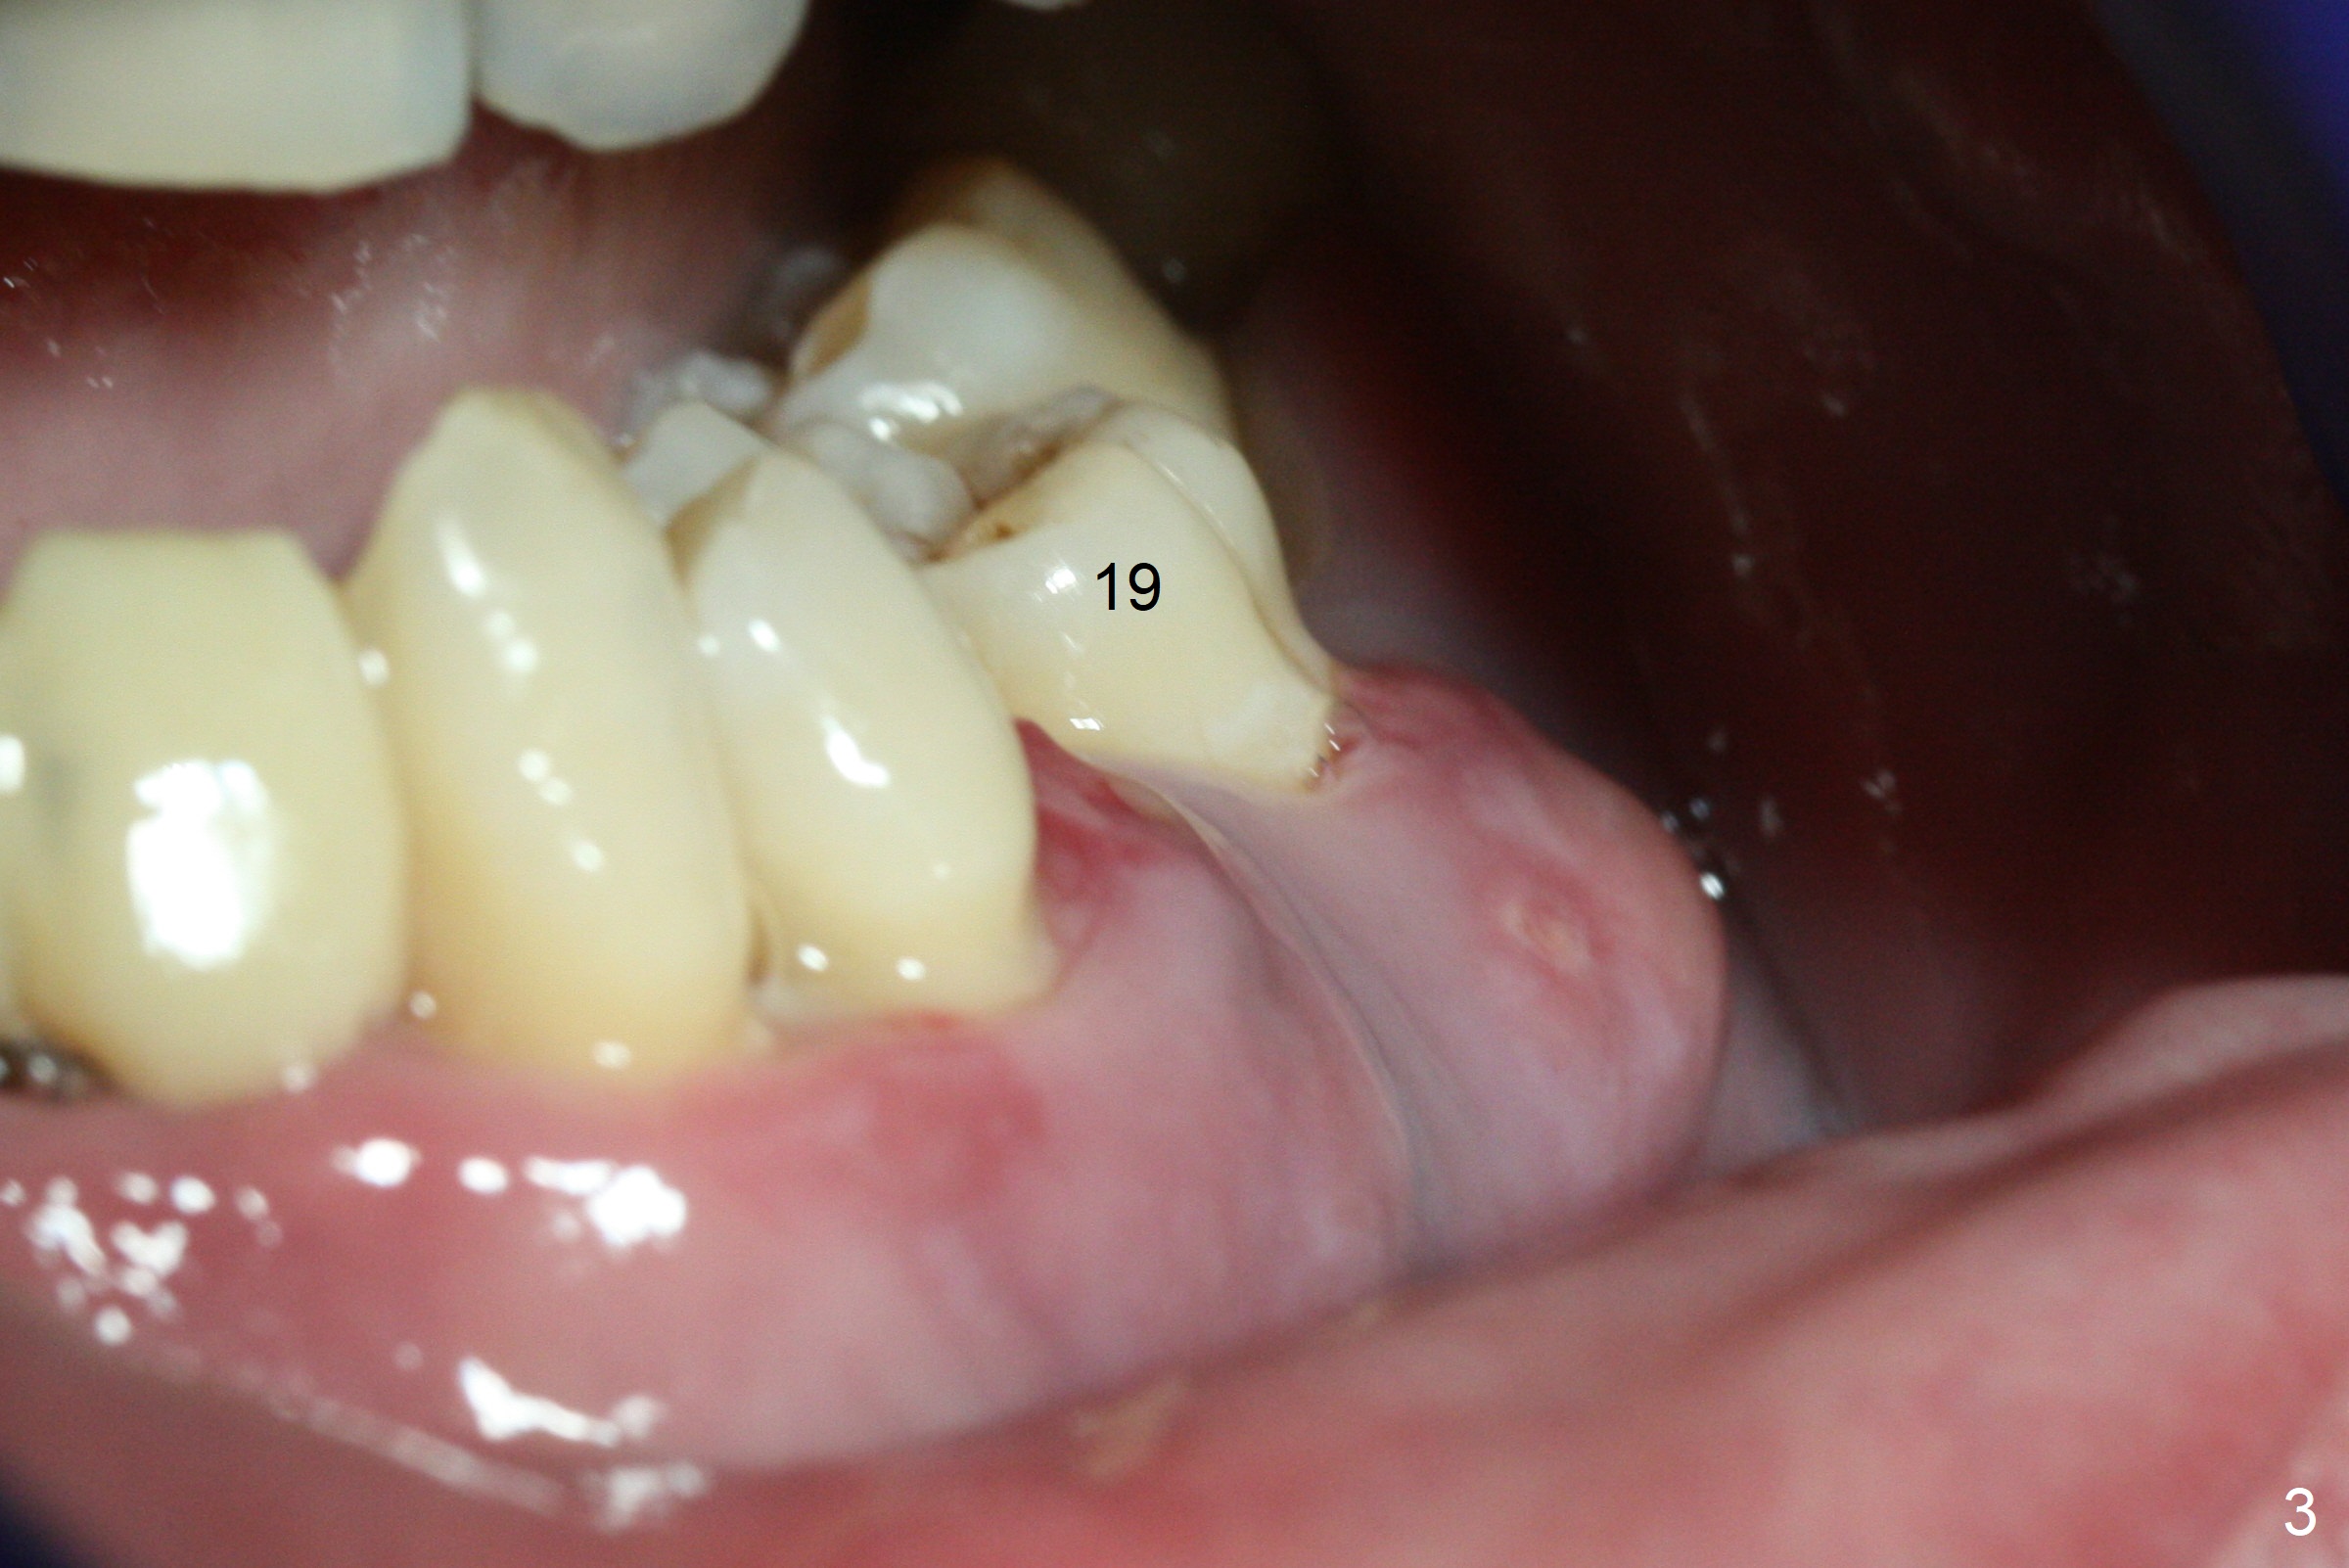

The 36-year-old man (ex-smoker, quit for 4-5 years) insists upon #3 and 5 extraction first for implants, in spite of more severe infection at #7, 14,19,30 (Fig.1-4). The gingiva around #23-26 implants is healthy 3 weeks postop (Fig.5). The initial depths at #3 and 5 are 8.5 mm (bone-level) and 18 mmm (gingiva-level (13 mm (implant length) + 5 mm cuff), respectively. When a drill penetrates the sinus floor, confirm the depth. After use of 3.8 mm drill, 4.5 mm tap drill is inserted at #3 without stability, while a 4.5x13 mm implant is placed at #5 with primary stability (Fig.6,7). Then a 5x11.5 mm is placed at #3 subcrestal proximally after sinus lift with Vanilla graft (without sinus membrane perforation; Fig.8). The implant at #5 is seated ~1 mm deeper (subcrestal mesially (^^); supracrestal distally (^)); allograft is placed around the implants prior to insertion of 6.5x7(5) and 5.5x4(5) mm abutments; last more allograft is added (Fig.9 *, 10). The implants seem to have been osteointegrated 4.5 months postop (Fig.11,12). The gingiva is healthy around the implants without bone loss 3 months post cementation (Fig.13,14).